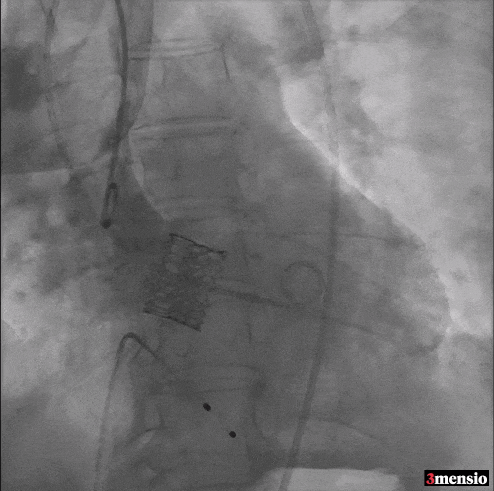

Step 3 瓣膜释放后造影

术后随访情况

术后复查超声心动图

术后CT随访情况